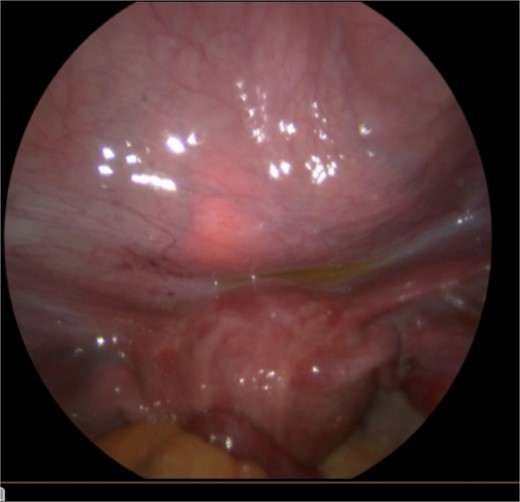

The patient was taken to the operating room for diagnostic laparoscopy, vaginoscopy, and cystoscopy. During laparoscopy (Fig. 2), minimal peritoneal fluid was observed, and no perforation was noted. Both the bladder and uterus appeared normal. Vaginoscopy findings were unremarkable. Cystoscopy (Fig. 1) revealed a normal urethra, with the lead pencil lying transversely within the bladder. The foreign body was successfully removed with forceps after multiple attempts (Fig. 3). Post-removal, a small injury site in the bladder wall was noted. The patient experienced a smooth postoperative recovery and was discharged with a Foley catheter after 2 days. Voiding urethrocystography conducted one week postoperatively indicated normal bladder capacity and contour, with no leaks, leading to the removal of the Foley catheter.